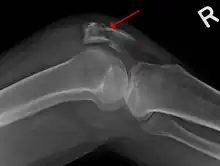

Vertical patella fracture

The patella can break in various ways depending on the way it is injured, and into two or more pieces.[1] Types include transverse, the most common, with one fracture line;[5] marginal; osteochondral; and the rare vertical type, or stellate, where a direct compression force gives rise to a comminuted pattern.[5][7] Patella fractures can be further classified as displaced, where the broken ends of bone do not line up correctly and separate by more than 2mm, or undisplaced and stable where pieces of bone remain in contact with each other.[1][7] If fragments of patella bone stick out from the skin it is known as an open patella fracture, and closed if the overlying skin is intact.[1]